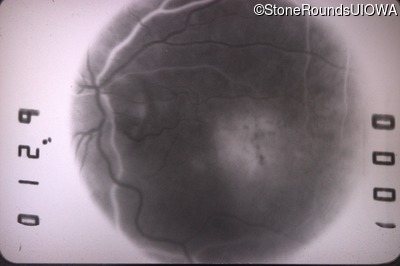

Fluorescein Angiography - Right - 20/25 +2

Exemplar